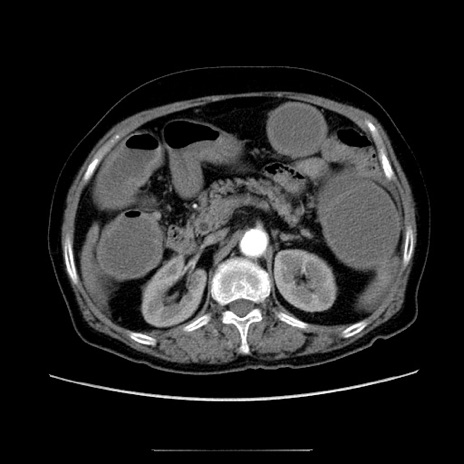

冠状断像

【症例】70歳代女性

【主訴】お腹が張る

【現病歴】1週間くらい前から腹部膨満の自覚あり。昨日夜から増悪したため、本日救急外来受診。

【身体所見】意識清明、BT 36.5℃、BP 165/106mmHg、HR 80bpm、SpO2 98%、腹部:膨満、軟、自発痛・圧痛なし、触診にて不快感あり、腸蠕動音:減弱

【データ】WBC 12600、CRP 1.04